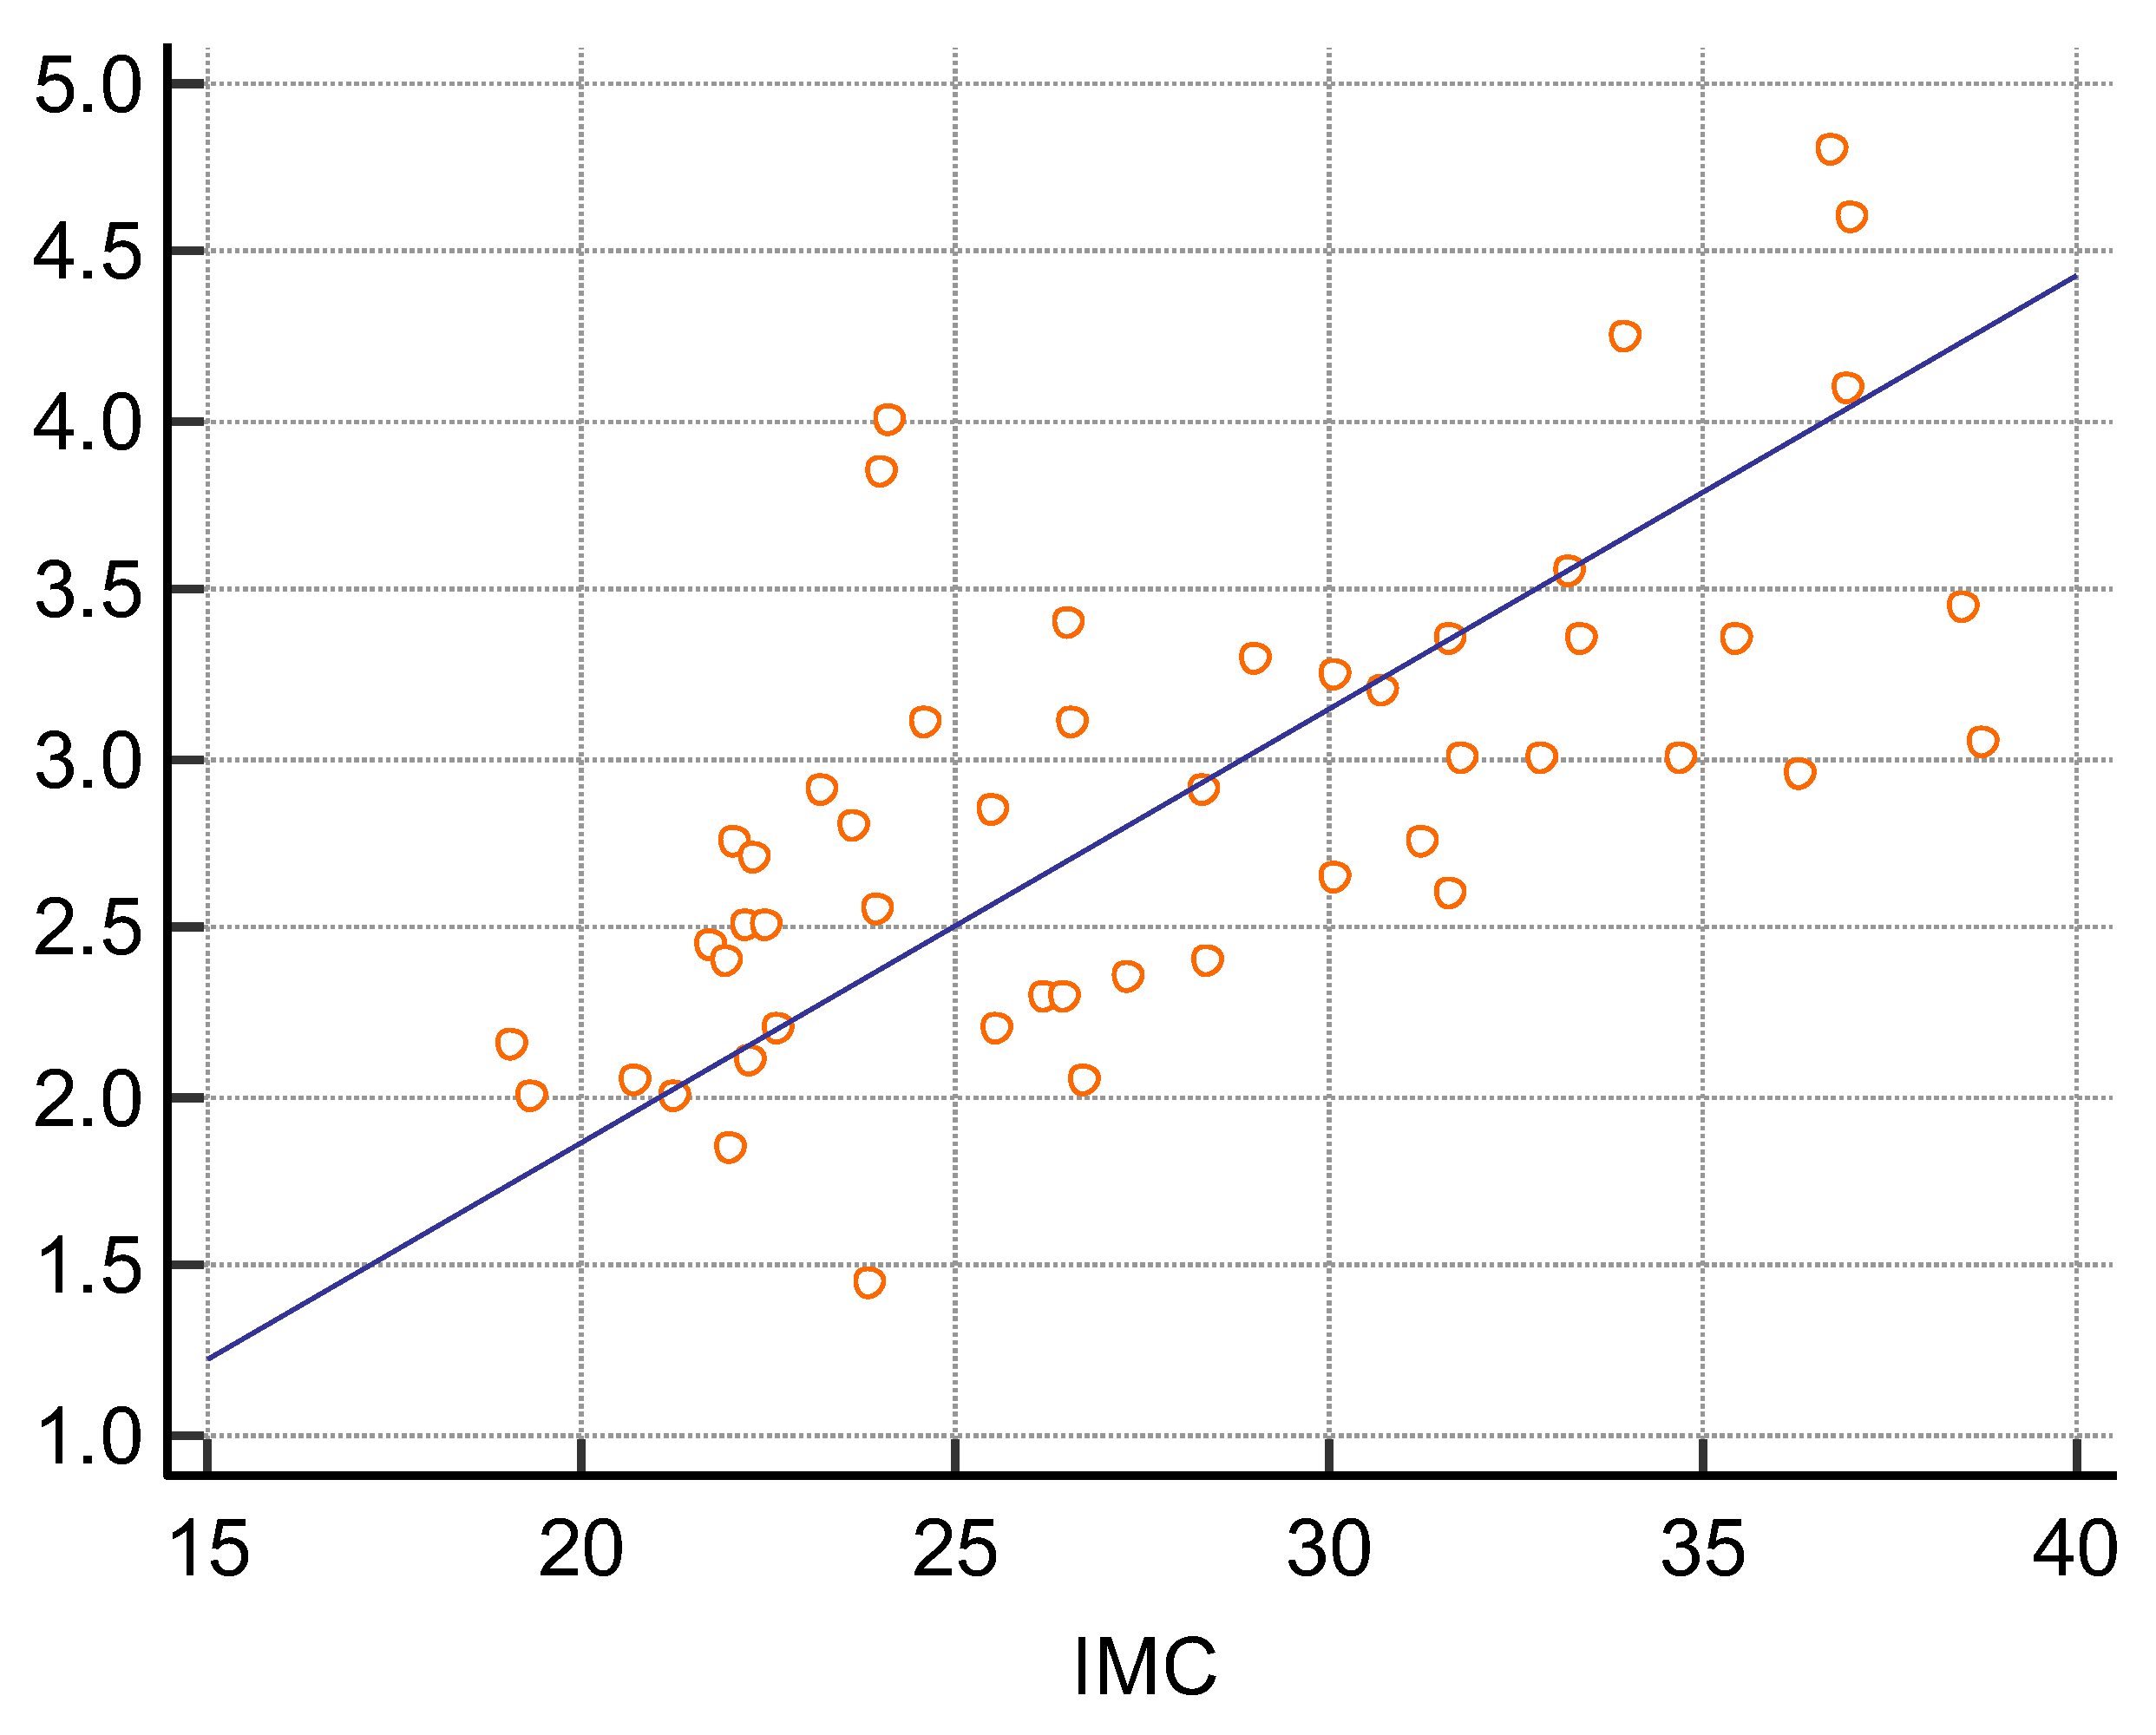

3. Results

| BMI | 27.8 ± 5.5 | −0.1738 | p = 0.2274 |